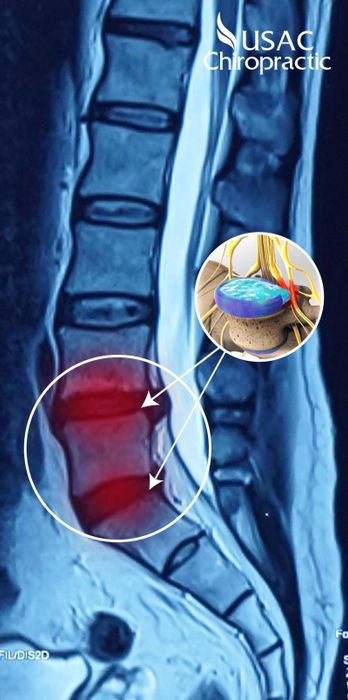

4. USAC Chiropractic

CallAs one of the leading American-standard musculoskeletal treatment centers in Vietnam, USAC is proud to own a system of clinics stretching from North to South with the most advanced equipment. Moreover, all doctors at USAC are from foreign countries with highly developed medical systems such as the USA, Europe, and Japan. This is the factor that helps USAC Chiropractic become confident and strong in the hearts of hundreds of thousands of patients. USAC Chiropractic has many years of strength in musculoskeletal diseases, focusing recently on developing solutions for general spine issues and spinal degeneration in particular.

'Selling trust and conviction' is the general mentality of patients when they know that USAC Chiropractic treats spinal degeneration, disc herniation with the Bone Power X4 protocol, guaranteeing no medication, no surgery, yet still reducing pain quickly. The Bone Power X4 protocol is designed and treated by the Joint Council of American and European Orthopedic Physicians with over 25 years of experience, providing 4 times more effective and faster treatment than other conventional methods, helping: Stop acute pain, adjust misaligned vertebrae, restore, restructure the entire spine, maintain, preserve a healthy spine.